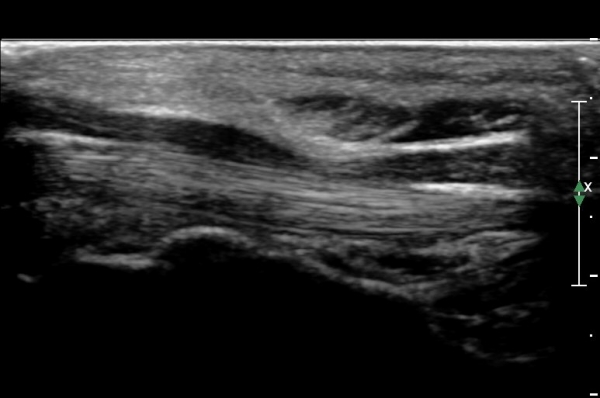

¼ö±Ù°ü ¸»´ÜºÎÀ§(trapezium, capitate level)¿¡¼ Á¤Á߽Űæ Ⱦ´Ü¸é°Ë»ç»ó Á¤Á߽ŰßÀÇ ÆíÆòȰ¡ °üÂûµÊ(»çÁø 3).

Á¤Á߽Űæ Á¾´Ü¸é°Ë»ç»ó ¼ö±Ù°ü ¸»´Ü(trapezium, capitate level) µÎ²¨¿öÁø Ⱦ¼ö±ÙÀδë(transverse carpal ligament)¿¡

ÀÇÇÑ Á¤Á߽ŰæÀÇ ±¹¼ÒÀû ¾Ð¹ÚÀÌ °üÂûµÊ(»çÁø 4, 5).